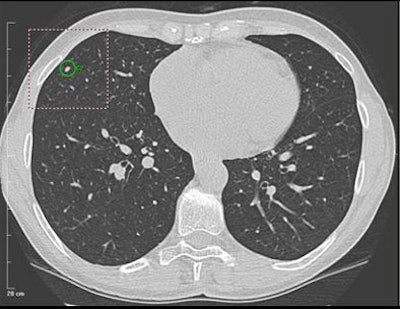

| Above: A 7-mm nodule in right middle lobe, representing a true-positive CAD finding. Below: A 5-mm nodule in the lower right lobe, representing a true-positive CAD finding. |